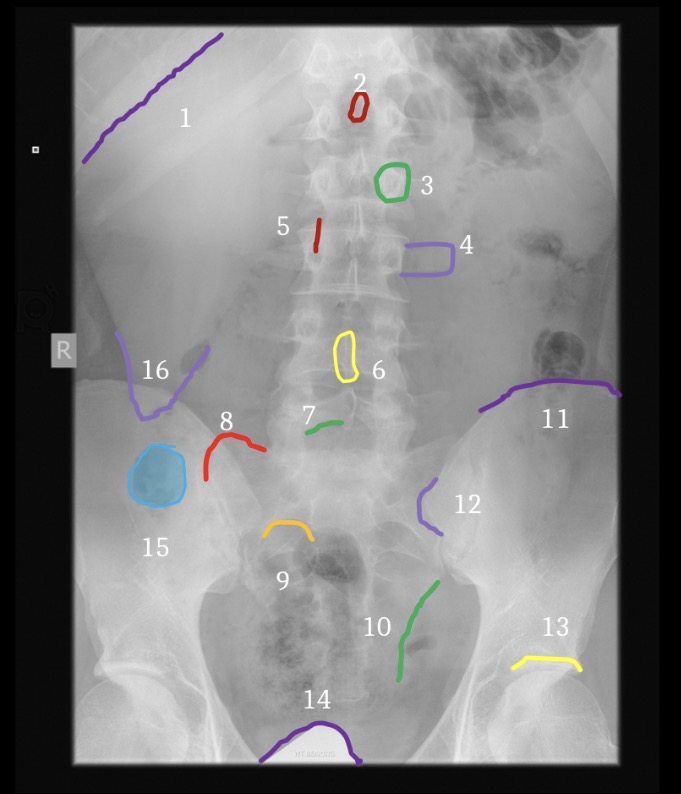

1

Right ilium

2

Left ilium

3

Right sacral ala

4

Left sacral ala